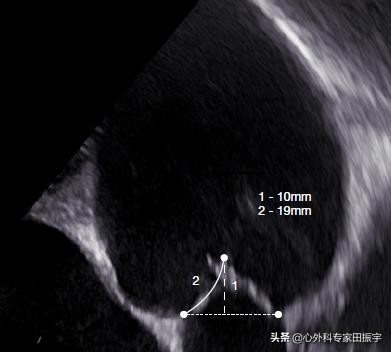

图2c:主动脉瓣舒张期的超声心动图。几何高度是通过测量从主动脉止点到游离缘的距离(19 Mm)来确定的。

图2c:主动脉瓣舒张期的超声心动图。几何高度是通过测量从主动脉止点到游离缘的距离(19 Mm)来确定的。有效高度由环形平面到自由尖端边缘的距离(10 Mm)确定。